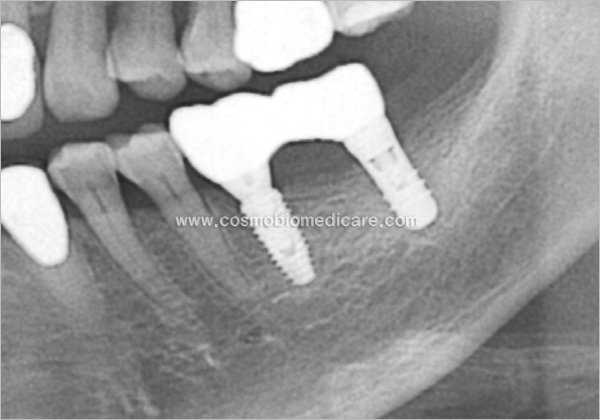

Clinical Cases

• Case1

• Case2

• Case3

• Case4

• Case5

• Case6

• Case7

• Case8

• Case9

• Case10